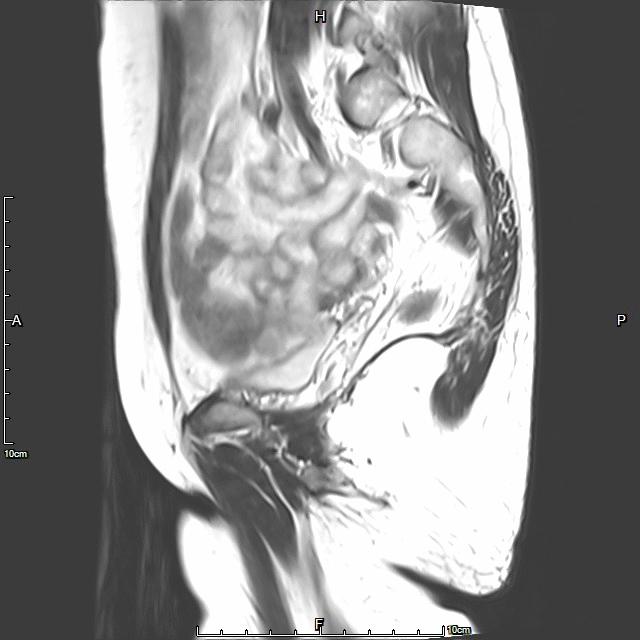

例3

中年患者,发现“子宫腺肌症”10年余,近5年痛经、月经量增多等症状明显加重,导致贫血,严重影响生活质量。

- 术前彩超、磁共振检查显示子宫明显增大,子宫前壁可见弥漫型子宫腺肌症病灶,合并粘膜下、肌壁间子宫肌瘤。

横断位

冠状位

矢状位

- 术后患者痛经、月经量过多症状迅速缓解,生活质量明显改善。